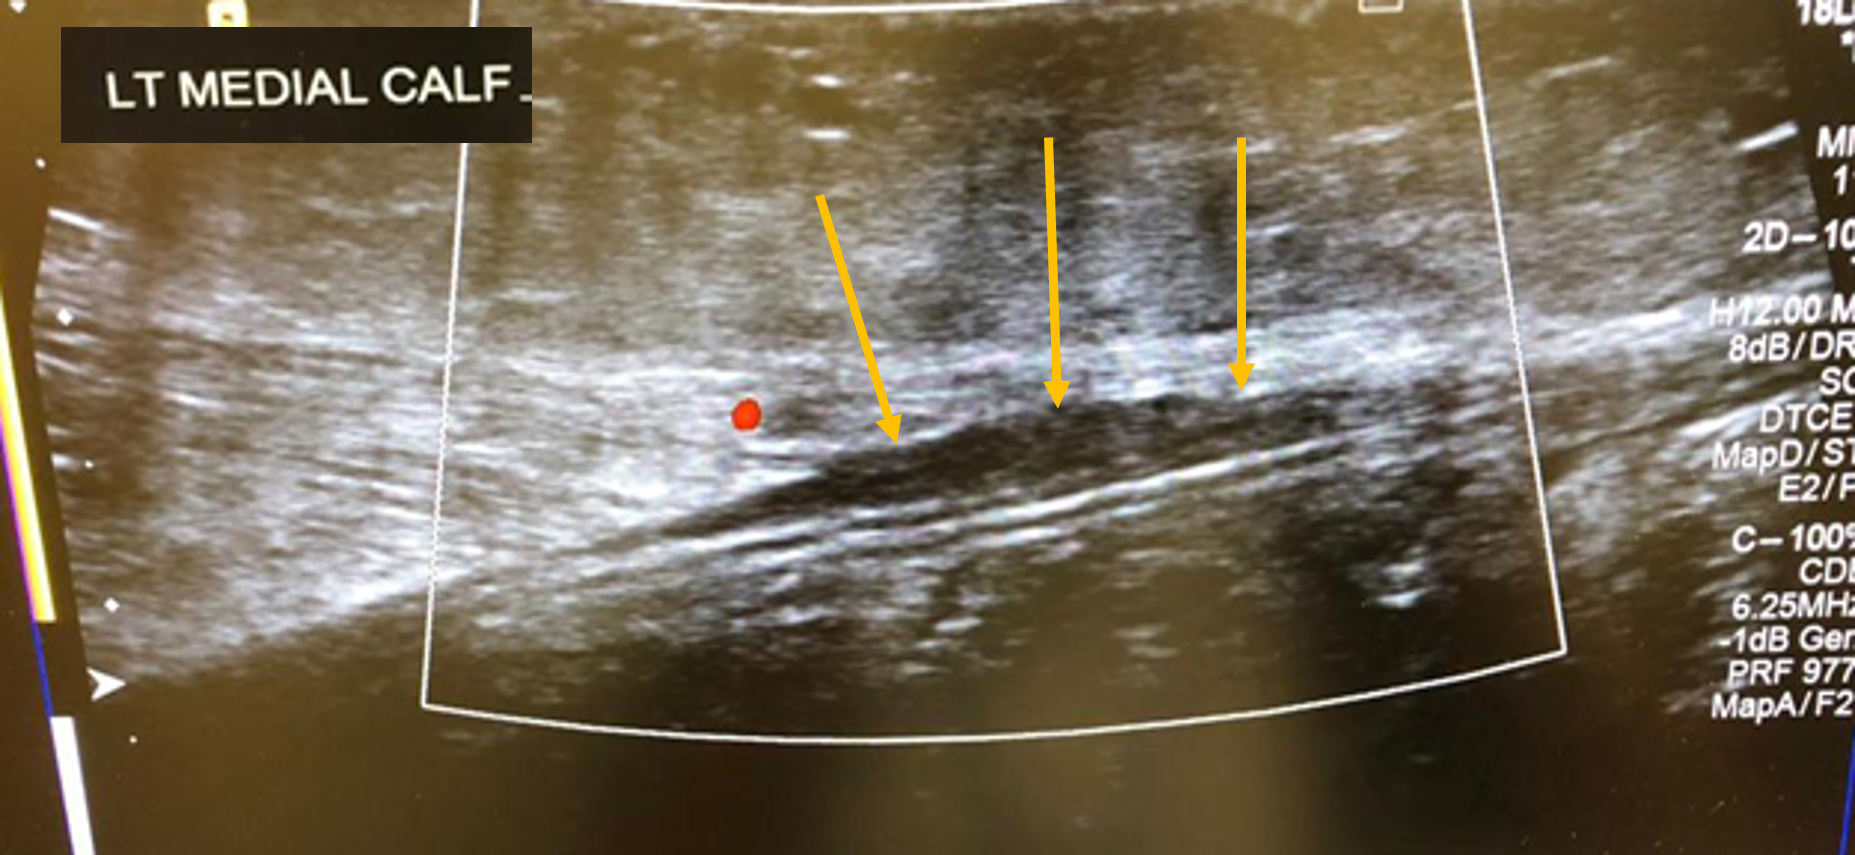

Although classically seen in people who play tennis, it can also be induced by playing squash, skiing, and athletics. Therefore, it typically occurs in active individuals. Extension of the knee and forced dorsiflexion of the ankle seem to be the most frequent biomechanical causes of the injury, which result in rupture of the medial head of the gastrocnemius muscle or injury to the gastrocnemius-soleus aponeurosis, without evidence of muscle rupture.

Ultrasound findings show a hypoechoic linear abnormality (yellow arrows).